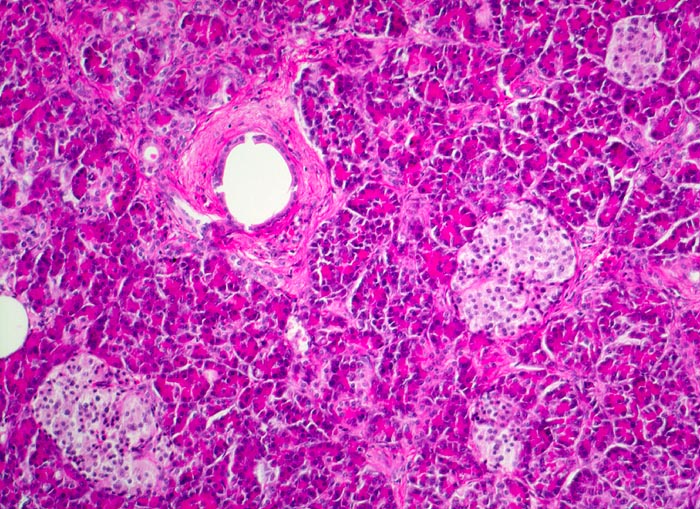

Fast alle exokrinen Drüsen sind betroffen. Pankreasgänge, intestinale Drüsen, intrahepatische Gallengänge und die Glandula submandibularis sind obstruiert durch visköses oder solides eosinophiles Material. Tracheobronchiale und Brunner’sche Drüsen bilden vermehrten Schleim. Schweissdrüsen, kleine Speicheldrüsen und Glandula Parotis sind histologisch normal, sezernieren aber vermehrt Natrium und Chlorid. Veränderungen in der Lunge ( 3689) entwickeln sich als Folge von Luftwegsobstruktion und Infekten (initial vor allem mit Staphylococcus aureus, später meist Pseudomonas aeruginosa).